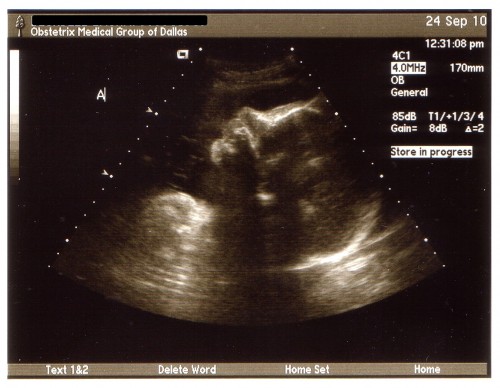

Here are some pictures of the boys’ profile from Friday…

Baby A - 33 weeks

Baby B - 33 weeks

On Friday we had our 33 week appointment with the perinatologist and our monthly growth scan of the boys. Everything looked great with the boys and they are growing just like they should, each of the boys gained a pound from 3 weeks ago! Baby A (Hayden) is now up to 4 lbs 3 oz and Baby B (Ian) is 3 lbs 14 oz….that’s 8 pounds of baby. The boys were both doing their practice “breathing” and moving around so we didn’t have to “taser” either of the boys this time. Baby A was being lazy again and took a little poking to get him to move around but he eventually did. Baby A is still head down (just like he has been for the last 8 months) and his body just kinda goes all along my right side while baby B is all curled up in a little ball. They couldn’t really tell us what position he was in, he wasn’t exactly breech or transverse, he was just kinda curled up. I’m going to guess he will be the one that likes to be swaddled up tightly. We will go back in another 4 weeks for our last growth scan but I’m kinda hoping we don’t make it to that appointment because they will already be here by then…one can hope, right?

We talked with the perinatologist and he was happy with their weights and amount of amniotic fluid. My cervix was the same as it was last Friday when I was at my OB’s office and he said as of right now the contractions aren’t doing a whole lot to it but that could change over night. He agrees with my OB that I should have a c-section at 37-38 weeks and not wait for 39 weeks like the hospital wants me to do. He said if I go into labor before next Thursday/Friday he (or my OB) would try to stop the labor and give me steroid injections to help give the boys’ lungs a boost. But one I reach 34 weeks (next week) the boys would do well enough if they were born that he wouldn’t stop labor. He said they would more than likely have to spend about a week in the hospital…but you never know until they are here. I will see my OB on Friday and then every week until they are here….which hopefully won’t be too much longer. I am so ready for them to get here….lack of sleep and all! But, as much as I want them here I hope they wait at least another week or 2, they need to grow a little bit more.